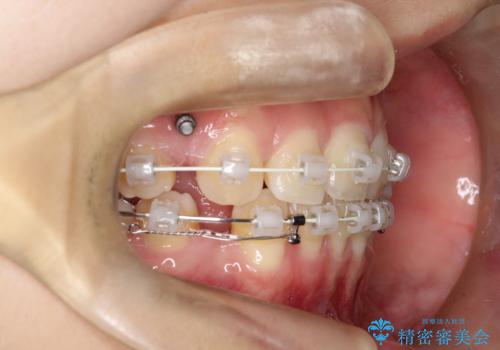

ワイヤーによる抜歯矯正でガタガタの改善

- 前歯のがたがたを主訴に来院されました。

上下の前歯が前方に傾斜しているのもあり、内側に前歯をひっこめるために上下左右の歯を1本ずつ抜歯して矯正することとしました。

ガタガタも改善しましたが、前歯が内側に引っ込むことにより口元もすっきりして、唇が閉じやすくなりました。